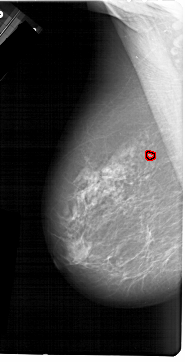

A_1214_1.RIGHT_CC

FILE: A_1214_1.LEFT_CC.OVERLAY

TOTAL_ABNORMALITIES 1

ABNORMALITY 1

LESION_TYPE CALCIFICATION TYPE PLEOMORPHIC DISTRIBUTION CLUSTERED

ASSESSMENT 4

SUBTLETY 4

PATHOLOGY MALIGNANT

TOTAL_OUTLINES 1

BOUNDARY